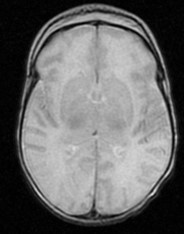

Segunda gestación gemelar de una madre sana de 40 años. Parto mediante cesárea electiva por cesárea previa a las 38 semanas de gestación. Nace segundo gemelo con prueba de Apgar 9/10/10; pHau:7.25. Peso de nacimiento: 3215g (p63), longitud: 49,5cm (p70) y perímetro cefálico: 34cm (p67). A las 60 horas de vida presenta empeoramiento clínico con alteración del estado de conciencia progresivo con mala coloración cutánea y alargamiento del tiempo de recapilarización. Presenta hipoglucemias mantenidas e inicia un estado epiléptico refractario al tratamiento con un pico febril al 7º día de vida. Se realiza RM cerebral ( Figura 1A, 1B) a las 39 semanas de EPM.

En la Figura 1A, se aprecia una pérdida de diferenciación entre córtex y substancia blanca, compatible con edema cerebral difuso, y en la Figura 1B se aprecia una disminución de la difusividad a nivel del córtex occipital derecho y parietal bilateral. Además nuestro paciente presentó hipoglucemias mantenidas los primeros días de vida que podrían explicar la lesión occipito- parietal hallada en la RM. Nuestro paciente fue exitus a los 9 días de vida por una enterocolitis fulminante.

Figura 1A. RM cerebral. Corte axial-T2-WI